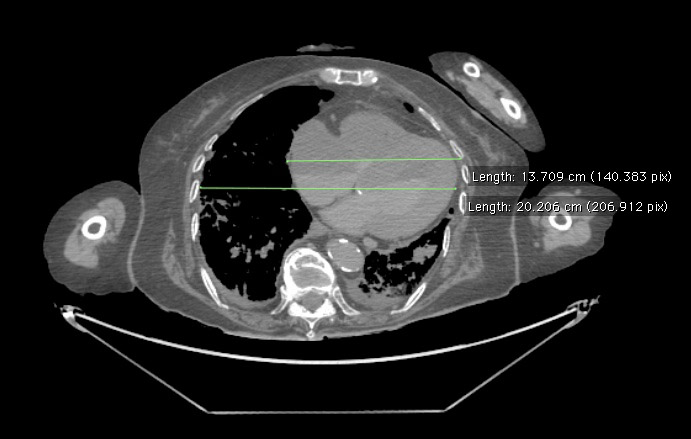

Cardiomegaly can also be diagnosed on CT scan. The screenshot below was taken from the postmortem CT scan of cadaver 33522. Using the medical imaging program Osirix, we measured this patient's CTR and found a heart width of 13.7 cm and a chest width of 20.2 cm, giving us a CTR of 13.7/20.2= 0.68 (this patient's largest horizontal chest width was actually below this cross section, but the difference in width was minimal and so we put both measurements on the same cross-section). Because a CTR less than 0.5 is considered normal, our CT scan indicates that this patient's heart is enlarged.

Image obtained from the Creative Commons database.